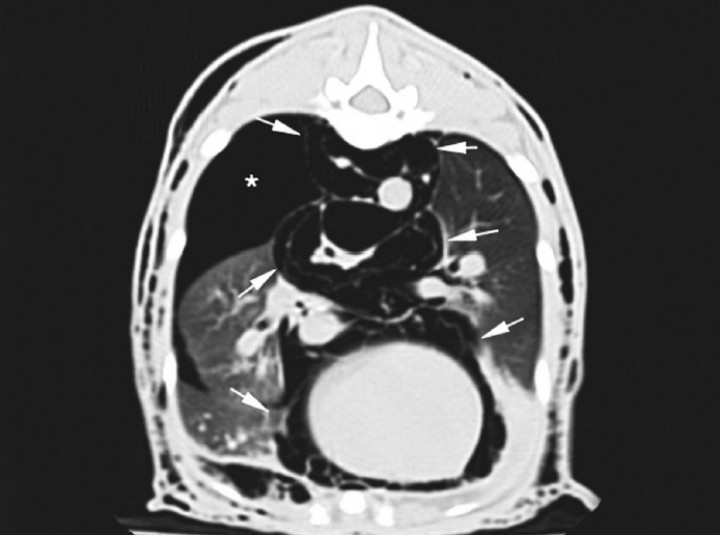

Para llegar a un diagnóstico definitivo podrían ser útiles una tomografía computarizada (TC) o una traqueobroncoscopia. En este caso debido a la historia clínica del paciente se decide hacer una TC. El estudio incluye dos series precontraste procesadas con algoritmos de tejido blando y pulmón, con cortes contiguos de 1 mm de grosor. Se observa dilatación marcada del mediastino con gas, o neumomediastino (Fig. 3), así como neumotórax y compresión de lóbulos pulmonares con atelectasia secundaria. El gas del mediastino se extiende a lo largo de los planos fasciales de los tejidos subcutáneos, causando enfisema muy marcado en cabeza, cuello, pared torácica y pared abdominal. El aire también se extiende caudalmente al espacio retroperitoneal (Fig. 4), cabeza (Fig. 5) y cuello (Fig. 6). Se detecta un pequeño defecto en la pared dorsal de la tráquea, aproximadamente a nivel de C7-T1 (Fig. 6B). Se observa mineralización a nivel del riñón derecho.

<p>Corte transversal de TC en ventana de pulmón. Se observa neumomediastino (flechas blancas) y neumotórax (asterisco blanco).</p>

Figura 3

Corte transversal de TC en ventana de pulmón. Se observa neumomediastino (flechas blancas) y neumotórax (asterisco blanco).